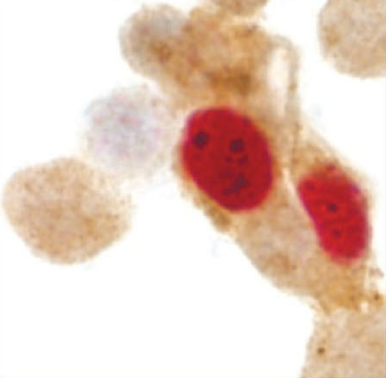

CINtec® PLUS Cytology, използвана в комбинация с cobas® HPV тест и CINtec® Histology, подпомага медицинските специалисти при вземане на решения, свързани с клиничната грижа за жените в риск от развитие на рак маточната шийка. Технологията за биомаркери с двойно оцветяване, включена в теста за цитология CINtec® PLUS, открива наличие на двата биомаркера – p16 и Ki-67, експресирани едновременно в рамките на една клетка. Тази аномалия е свързана с HPV инфекции, които се трансформират и могат, ако не бъдат лекувани, да прогресират до предракови заболявания или рак. Положителният резултат от тези два биомаркера, експресирани в една и съща клетка, сигнализира за по-висок риск от развитие на заболяване.

Едновременна експресия на р16 и Кі67 CINtec

Едновременна експреси на р16 и Кі67 CINtec